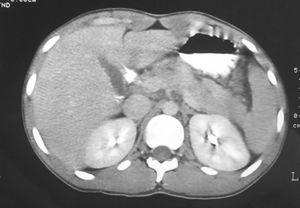

Fig. 1. Tomografía computarizada con contraste intravenoso realizada 3 días después del ingreso del paciente, donde se aprecia un aumento de tamaño de la glándula pancreática, así como una discreta pérdida de definición de sus límites, sin evidencia de colecciones peripancreáticas ni de necrosis glandular.

OBSERVACIÓN CLÍNICAVarón de 17 años que acudió a urgencias de nuestro hospital en junio de 2003 por presentar dolor abdominal epigástrico de varias horas de duración, irradiado al hipogastrio y acompañado de sensación nauseosa y vómitos. El día anterior había tenido molestias abdominales que remitieron con la ingesta. No refería alteración del ritmo intestinal ni presencia de productos patológicos en las heces. No consumía alcohol ni otras drogas y únicamente unos días antes del comienzo de la clínica había seguido un tratamiento con antihistamínicos (loratadina) por un cuadro catarral.En agosto de 2002, el paciente estuvo ingresado en otro centro hospita lario por un episodio de pancreatitis aguda alitiásica de origen no filiado. Durante ese ingreso se efectuaron, entre otras pruebas, una ecografía y una TC abdominal, sin que se objetivasen hallazgos significativos. La exploración física realizada en urgencias revelaba únicamente la existencia de dolor a la palpación en el epigastrio, la zona periumbilical y el flanco derecho sin irritación peritoneal, con práctica ausencia de los ruidos hidroaéreos intestinales. Analíticamente presentaba en el hemograma una ligera leucocitosis (15,1 × 10 3 /µl) con neutrofilia (83%), y en la bioquímica unas cifras de amilasa de 3.971 U/l (25-125 U/l) con un perfil hepático sin alteraciones. La ecografía de urgencias mostraba un páncreas aumentado de tamaño, con edema peripancreático, sin observarse colecciones ni colelitiasis. El paciente ingresó en el Servicio de Gastroenterología para estudio con el diagnóstico de pancreatitis aguda recidivante de origen no filiado. Una vez en planta, se completó el estudio analítico; la proteína C reactiva a las 48 h fue de 93 mg/l (≤ 8 mg/l), y no se hallaron otros datos significativos en el análisis de los iones, la parathormona, el lipidograma, el proteinograma, las inmunoglobulinas y los autoanticuerpos. En una TC abdominal se confirmó el aumento de tamaño de la glándula pancreática y se descartaron posibles complicaciones asociadas (fig. 1). Se realizó una ecoendoscopia, que también mostró imágenes compatibles con pancreatitis aguda, sin datos de páncreas divisum . El paciente se trató con medidas convencionales, y presentó una buena evolución, por lo que fue dado de alta a las 2 semanas del ingreso. Dado que, a pesar de todas las exploraciones complementarias realizadas, todavía no se había aclarado el posible origen de la pancreatitis y se trataba del segundo episodio en un paciente joven, se obtuvieron muestras de sangre para determinar la existencia de mutaciones en el gen CFTR (mediante Genotyper ® Cystic Fibrosis Diagnosis System, PE Applied Biosystem, CA, EE.UU.). Se identificaron las mutaciones P5L y P205S, ambas asociadas a formas moderadas de FQ (genotipo P5L/P205S) y descritas con anterioridad en la población española (www.genet.sick-kids.on.ca/cftr/) 4 . También de forma ambulatoria se realizó una colangiorresonancia magnética con secretina por vía intravenosa, que demostró un conducto de Wirsung normal. Habiendo descartado otras causas de pancreatitis aguda, y teniendo en cuenta las 2 mutaciones del gen CFTR detectadas en nuestro paciente, se hizo el diagnóstico de FQ con inicio en forma de pancreatitis aguda recidivante. En los 11 meses posteriores al diagnóstico el paciente ha estado asintomático, únicamente con dieta pobre en grasas y abstinencia alcohólica. Se ha completado el estudio de FQ por parte del Servicio de Neumología de nuestro centro. El test del sudor ha sido negativo (44 mEq/l de cloruro), la espirometría evidenció una función pulmonar normal y la TC torácica de alta resolución descartó la presencia de bronquiectasias. También se le realizó un seminograma que fue normal. En una segunda anamnesis dirigida tras conocer el diagnóstico de FQ el paciente refirió clínica de congestión nasal y rinorrea mucopurulenta de años de evolución. Por este motivo se solicitó una valoración otorrinolaringológica, donde se detectaron pólipos nasales. También se le realizó una TC de cara y cuello en la que se halló una ocupación del seno maxilar izquierdo, del meato medio ipsilateral y una ocupación parcial del seno maxilar derecho compatible con un quiste de retención.